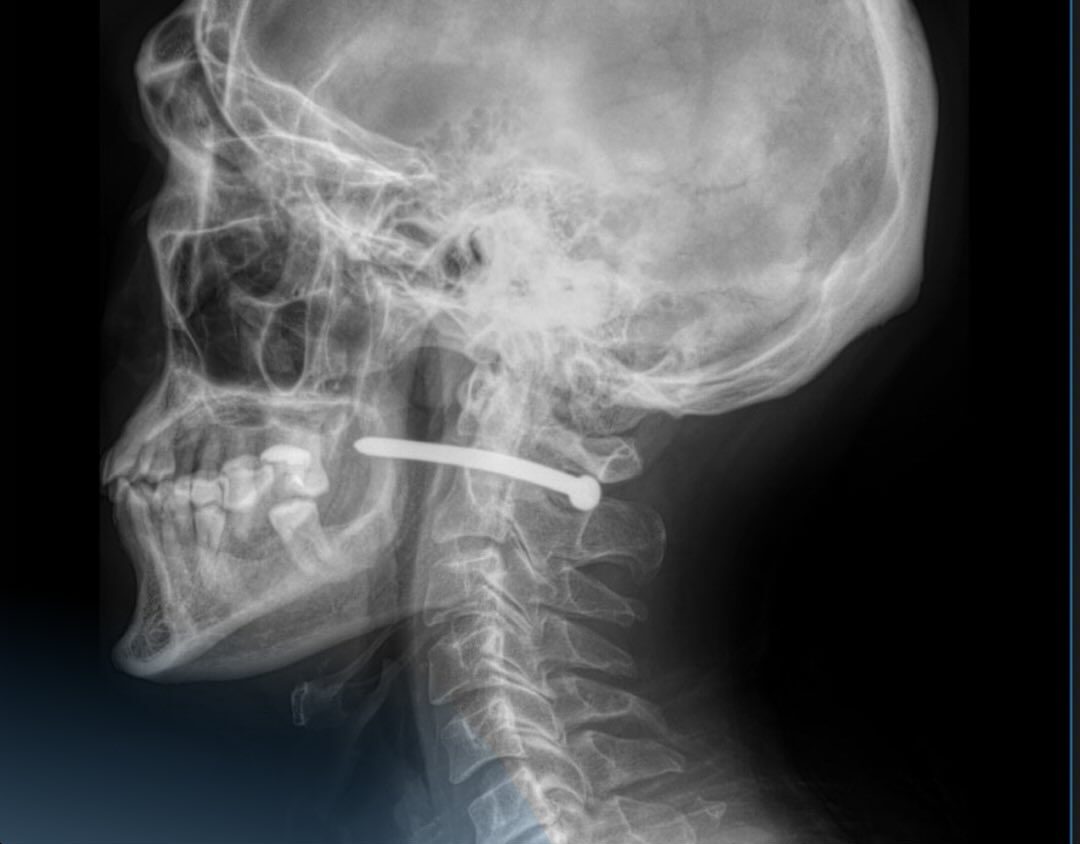

Құрылыс жөндеу жұмыстары кезінде шегеге арналған пневматикалық құралдың шегесі ер адамынң құлақ сыртына қадалыпты. Рентген-зерттеуден кейін шегенің омыртқаның мойын бөлігінен өткені анықталды. Тұрғынның көрер жарығы бар екен – өміріне маңызды органдары зақымдалмапты.

«Жақсүйек-бет хирургтары сүйектен шегені алып, жараны өңдеді. Жара тігіліп, стерильді таңғыш салынғаннан кейін пациентке ұсыныстар беріліп, ол үйіне жіберілді. Мойын тұсына жарақат алу өте қауіпті. Мойынның маңайынан үлкен тамырлар, нервтер, тыныс алу жолдары және жұлын өтеді. Тіпті кішкене ғана зақым алудың салдары ауыр болуы мүмкін еді»,-дейді дәрігерлер.